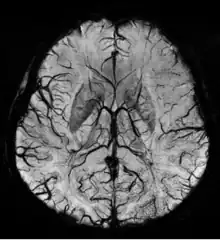

Vascular dementia and cerebral amyloid angiopathy (CAA)

Gradient recalled echo (GRE) imaging is the conventional way to detect hemorrhage in CAA, however SWI is a much more sensitive technique that can reveal many micro-hemorrhages that are missed on GRE images.[7] A conventional gradient echo T2*-weighted image (left, TE=20 ms) shows some low-signal foci associated with CAA. On the other hand, an SWI image (center, with a resolution of 0.5 mm x 0.5 mm x 2.0 mm, projected over 8mm) shows many more associated low-signal foci. Phase images were used to enhance the effect of the local hemosiderin build-up. An example phase image (right) with yet higher resolution of 0.25 mm x 0.25 mm x 2.0 mm shows a clear ability to localize multiple CAA-associated foci.